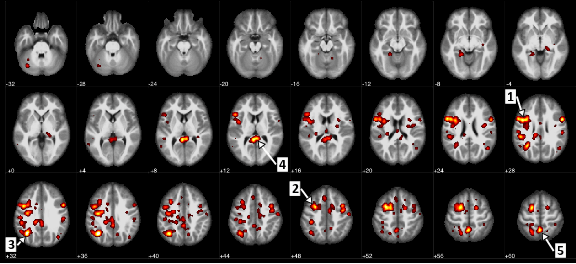

Regions of the brain that showed a statistically significant difference between patients with schizophrenia and patients without it. (Arrow 1 identifies the precentral gyrus, or the motor cortex, and arrow 5 marks the precuneus, which involves processing visual information.)

In the paper, researchers analyzed de-identified brain functional Magnetic Resonance Imaging (fMRI) data from the open data set, Function Biomedical Informatics Research Network (fBIRN) for patients with schizophrenia and schizoaffective disorders, as well as a healthy control group. fMRI measures brain activity through blood flow changes in particular areas of the brain. Specifically, the fBIRN data set reflects research done on brain networks at different levels of resolution, from data gathered while study participants conducted a common auditory test. Examining scans from 95 participants, researchers used machine learning techniques to develop a model of schizophrenia that identifies the connections in the brain most associated with the illness.

The results of the IBM and University of Alberta research demonstrated that, even on more challenging neuroimaging data collected from multiple sites (different machines, across different groups of subjects etc.) the machine learning algorithm was able to discriminate between patients with schizophrenia and the control group with 74% accuracy using the correlations in activity across different areas of the brain.